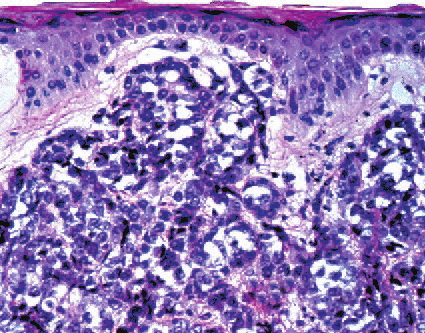

metastasis